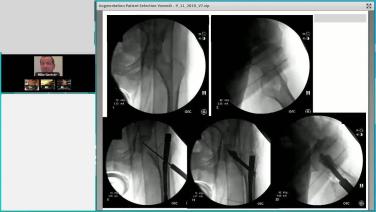

Augmenting Geriatric Hip Fractures: Failure Modes with Matthew Graves, MD

Augmenting Geriatric Hip Fractures: Reduction & Augmentation Techniques with Greg Osgood, MD

Augmenting Geriatric Hip Fractures: Biomechanical & Clinical Literature Review for TRAUMACEM V+ with Michael Leslie, DO

Managing Geriatric Hip Fractures Case Review with Michael Blauth, MD

Augmenting Geriatric Hip Fractures: Logical Indications Through Case Examples with Michael Gardner, MD